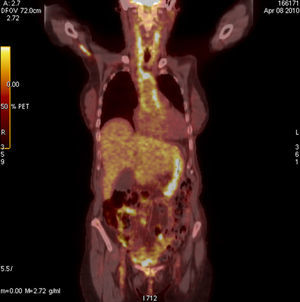

Caso clínico 1Mujer de 43 años con antecedentes de sinusitis crónica, úlceras corneales y blefaritis de repetición, en tratamiento con 30mg de prednisona al día tras haber sido estudiada en la unidad de enfermedades infecciosas por febrícula vespertina persistente de 37,5°C, donde se descartó origen microbiológico. Pasadas unas semanas de mejoría clínica ingresa en reumatología por fiebre de hasta 39°C de 15 días de evolución, que cedía con antipiréticos, cifras de tensión arterial (TA) de 100/60mmHg y parestesias en pie izquierdo, por lo que se realizó un estudio neurofisiológico que demostró un patrón electroneurográfico de bloqueo de la conducción a nivel distal del tibial posterior izquierdo, compatible con la vasculitis del sistema nervioso periférico. En la analítica destacaba una discreta leucocitosis con mínima desviación a la izquierda, velocidad de sedimentación globular (VSG) de 97mm (valores normales hasta 25mm) y proteína C reactiva (PCR) de 1,22mg/dl (normal hasta 0,5mg/dl) siendo el estudio de autoanticuerpos -incluyendo los anticitoplasma (ANCAS)-, negativo. Se realizó estudio de líquido cefalorraquídeo que mostró pleocitosis leve constituida por linfocitos. La primera sospecha clínica fue de poliarteritis nodosa (PAN), por lo que se decidió realizar una biopsia muscular y del nervio sural que resultó inespecífica. Por su antecedente de sinusitis se pensó en una poliangitis con granulomatosis o granulomatosis de Wegener (GW), por lo que se solicitó una biopsia de mucosa afectada que la descartó. En todo momento los pulsos periféricos permanecieron presentes y simétricos, sin diferencias significativas de la TA entre ambos brazos, no se detectaron soplos a la auscultación de aorta ni subclavias y la paciente no refería clínica de fatiga o malestar muscular con los movimientos que sugiriese claudicación. A los 10 días de ingreso comienza con cefalea occipital y frontal con fotofobia resistente a tratamiento analgésico y crisis hipertensivas (160/95mmHg) que cedían con la administración de IECA. Manteniendo nuestra sospecha clínica de vasculitis realizamos una angiorresonancia magnética (ARM) de aorta (Ao) −que no mostró alteraciones−, una RMN cerebral donde se comprobó la existencia de paquimeningitis y un TAC toracoabdominal que mostró un pequeño aneurisma infrarrenal de 2cm de diámetro. Por último, se realizó un PET-TAC que mostró lesiones hipermetabólicas en cono y bifurcación pulmonar, así como en la pared de la Ao abdominal (fig. 1), que junto con el sexo, la edad, la afectación de vasos de gran tamaño (Ao y pulmonar), la presencia de aneurismas, la negatividad de los ANCAS y la exclusión mediante biopsia de PAN y GW, hacen muy probable el diagnóstico de enfermedad de Takayasu (ET) ante la dificultad de realizar biopsia de la zona afectada.